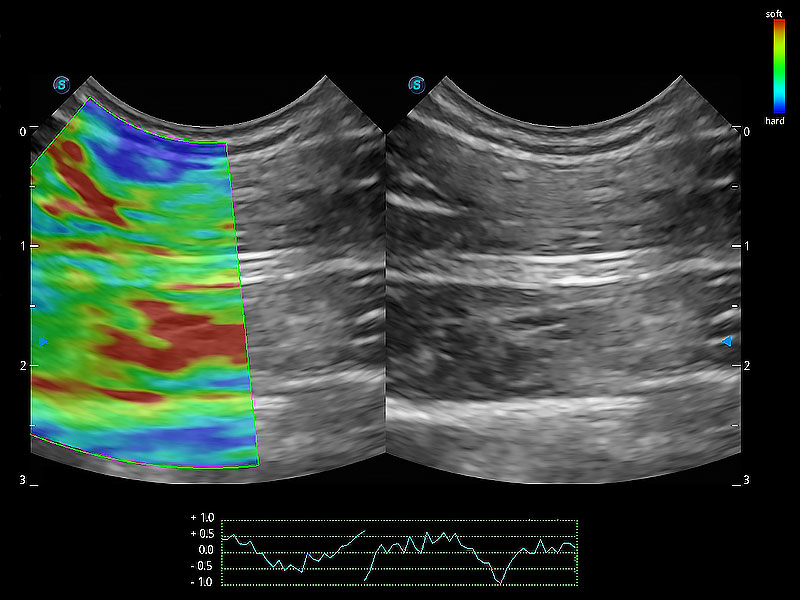

操作簡(jiǎn)便,無(wú)需高頻度外力作用即可真實(shí)反映組織的形變,快速評(píng)估腫瘤良惡性。